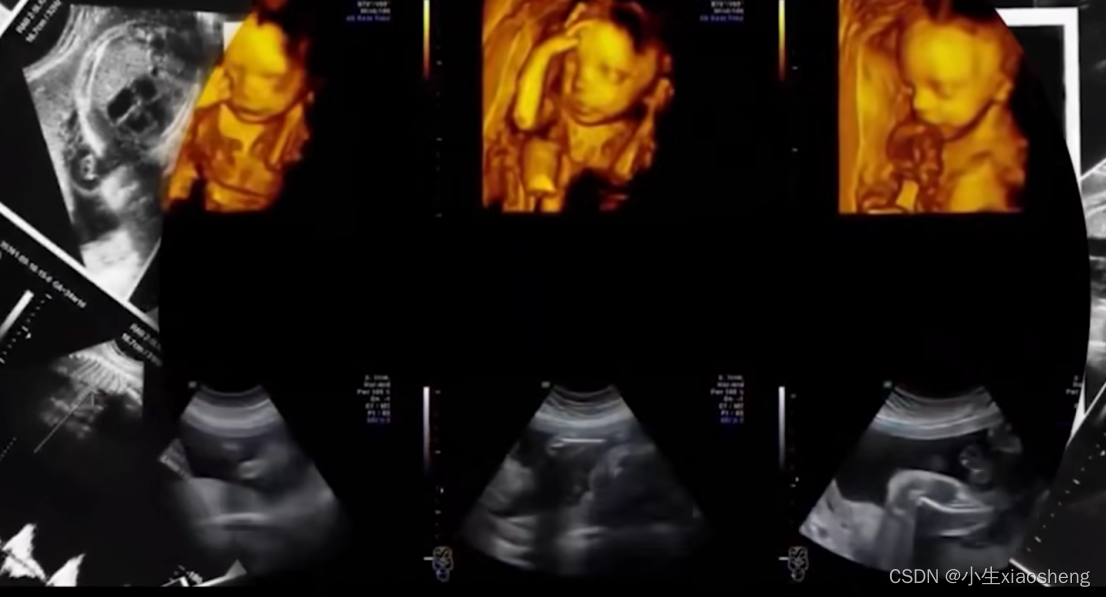

B超:超声用的是反射,超声设备会先对人体释放超声波,然后根据人体器官反射出来的回声为器官画像,超声对人体软组织和血管探测能力较强,所以内脏之类的很适合用超声。